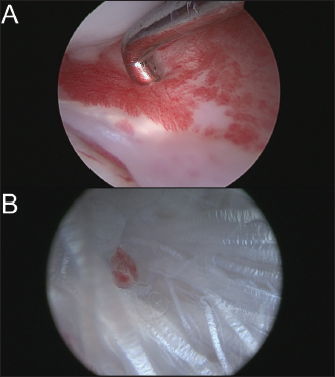

The dog was anesthetized with tiletamine (0.5 mg/kg)/zolazepam (0.5 mg/kg) + medetomidine (0.01 mg/kg) + morphine hydrochloride (0.5 mg/kg) by induction. An isoflurane relay (between 0.8 and 1%) in half-closed circuit was carried out at a flow rate of 1 l/minute. A constant rate infusion (2 ml/kg/hour) of a mixture of 250 ml of physiological serum + 30 mg of morphine + 202.75 mg of lidocaine + 75 mg of ketamine was administered. A single injection of cephalexin at 30 mg/kg was given at the start of the surgical preparation. The dog was placed in dorsal recumbency and prepared for aseptic surgery on the right hindlimb using chlorhexidine. A joint distractor supported by two 2.5-mm pins was placed on the stifle. The arthroscopic port was placed on the lateral side through a 5-mm lateral parapatellar incision performed with an 11-mm blade. Arthroscopic evaluation of the joint revealed inflammation of the medial meniscus without structural damage (Fig. 2A) and confirmed the complete rupture of the CdCL in its distal part at the tibial insertion (Fig. 2B). The lateral meniscus and the cranial cruciate ligament were intact. The lateral parapatellar incision was made 3 cm wider to allow the complete resection of the damaged CdCL with an 11-mm blade under arthroscopic control. The bone tunnels for femoral and tibial fixation of the synthetic ligament were drilled under arthroscopic control. A 2-mm guide wire was inserted at the femoral footprint of the origin of the CdCL in a caudo-medial direction to exit on the medial side of the femoral condyle under arthroscopic guidance. The femoral tunnel was drilled over the guide wire using a 3.6-mm cannulated drill bit (Fig. 3A). The tibial tunnel was created with the help of a tibial drilling guide. A stab incision was made at the caudal aspect of the joint to insert the tip of the tibial drilling guide, which was positioned at the footprint of the proximal tibial insertion of the CdCL under arthroscopic control, and oriented in a distal and cranio-lateral direction. A stab incision was made on the proximal aspect of the craniolateral aspect of the tibia to position the sleeve of the drilling guide. The appropriate position of the tip of the tibial drilling guide was assessed arthroscopically before drilling. The same technique as that used for the femoral tunnel was used to drill the tibial tunnel (Fig. 3B). The UHMWPE implant (Novalig 4000, Novetech Surgery, Monaco) was passed through the tibial and femoral tunnels using a passing tube and a wire loop (Fig. 4A). A 4.5 × 20-mm interference screw was placed from inside-out (Fig. 4B) (Rafael et al., 2020). The UHMWPE implant was then passed through a 3-mm-wide sliding tunnel, drilled perpendicularly through the tibial crest using a medial approach and located near the distal exit of the tibial tunnel. This setup increased the precision of the tensioning of the prosthesis using the created counter-support and facilitated the placement of the interference screw. Once satisfactory tension was obtained, the implant was locked with a second 4.5 × 20-mm interference screw placed from outside-in (Fig. 4C) (Rafael et al., 2020). Once the implant was securely locked, no residual drawer sign was observed and a normal range of motion was reported.

Fig. 2. (A) Arthroscopic view of inflammation of medial meniscus without structural damage. (B) Arthroscopic view of ruptured CdCL.